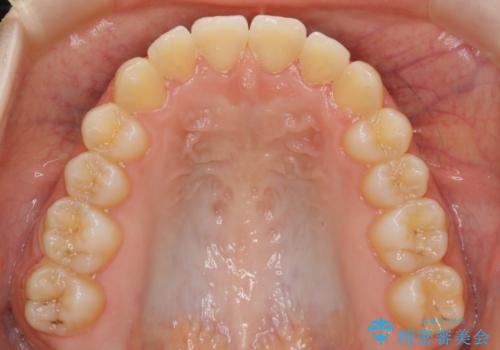

【非抜歯】すきっ歯と噛み合わせの治療

- 上の前歯のすきっ歯と下の前歯のガタつきを主訴にご来院されました。

噛み合わせの改善も同時に進めつつ、主訴の部分も効率的に治していくためマウスピース装置でゴムかけを行いながら治療を進めていきました。

正中離開(すきっ歯)

真ん中の歯が左右に開いてしまい隙間ができてしまう状態を「正中離開」といい、俗にすきっ歯と呼ばれています。

隙間を埋めていく方向に歯を移動させることで改善していくケースが多く、比較的治りやすい不正咬合のひとつとされています。

しかしながら、歯が捻じれていたり、噛み合う歯との位置関係によっては治療が難しくなる場合があります。